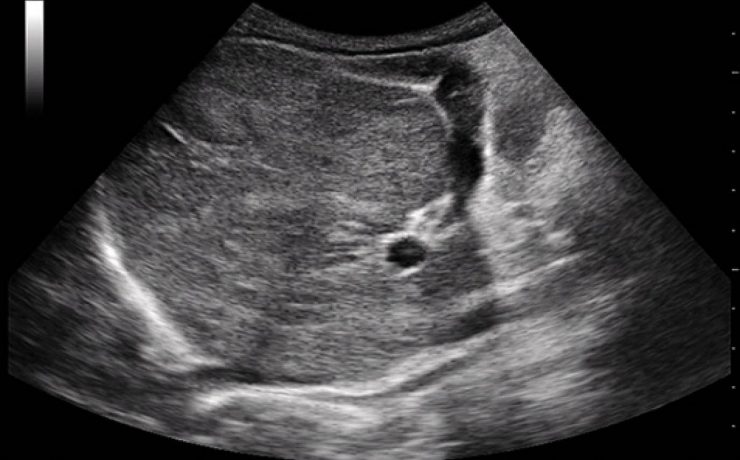

Vesícula biliar y vías biliares

La patología de la vía biliar habitualmente se presenta en la clínica como ictericia o alteración de las enzimas hepáticas, con o sin dolor abdominal o fiebre. La ecografía suele ser la primera prueba de imagen que se realiza, con la intención de discriminar si el paciente presenta una enfermedad